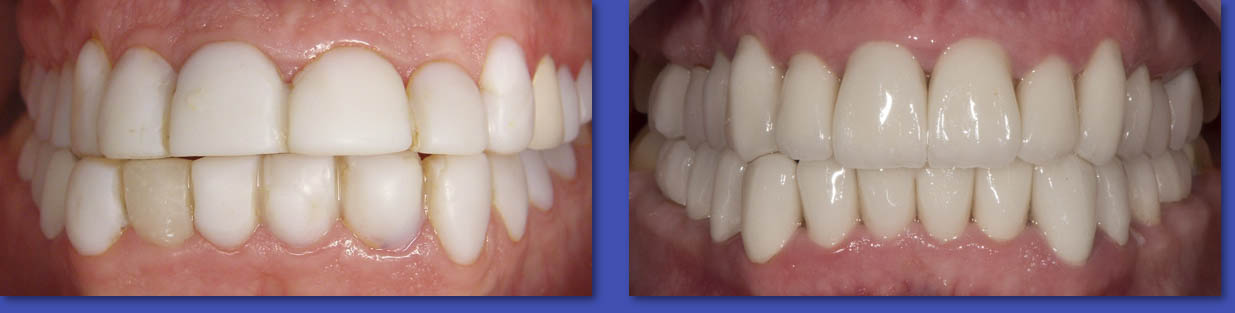

9. ESTÉTICA DENTAL

La estética  actualmente, en nuestra sociedad marca la diferencia. Una bella sonrisa ( con dientes hermosos y sanos ) nos abre puertas en  todo lugar y circunstancia, de ahí la importancia. Una sonrisa perfecta se puede lograr recurriendo a procedimientos de :  Blanqueamiento o Clareamientos dentales, Carillas de Cerámica, Ortodoncia, Remodelación de encías,etc.

ANTES

DESPUÉS